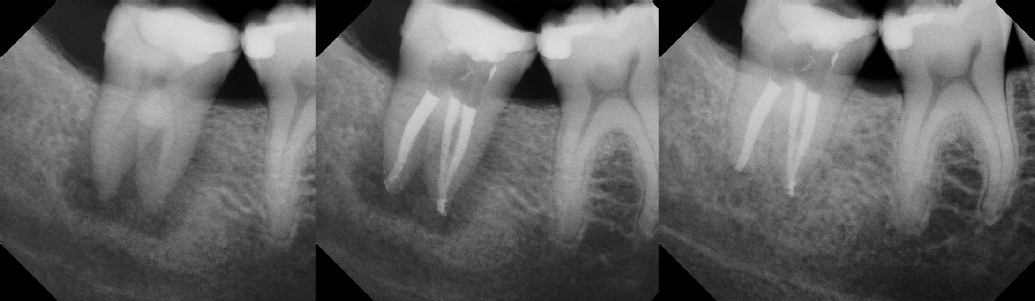

Pre-op Post-op 6 mos.